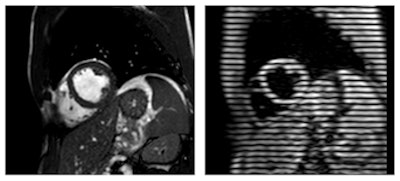

The study group compared baseline images with those obtained after one hour using cardiac MRI with complementary spatial modulation of magnetization (CSPAMM).

Cardiac MRI with CSPAMM revealed significantly increased peak strain and peak systolic strain rates, which reflect contractility, in the left ventricle. CSPAMM also showed that stroke volume -- the amount of blood pumped from the left ventricle -- increased after energy drink consumption due to the higher peak systolic strain.

Images show a cross-section of the heart using common MRI techniques (left), compared with the tagged myocardium using CSPAMM (right). Images courtesy of RSNA and Dr. Jonas Dörner.As part of the study, the researchers also assessed the effect of a caffeine-only drink (iced coffee) with the same amount of caffeine as the energy drink in nine participants. Scans were once again obtained before and after consumption, and this part of the study was performed two to three weeks after the energy drink portion, so there would be no residual impact.